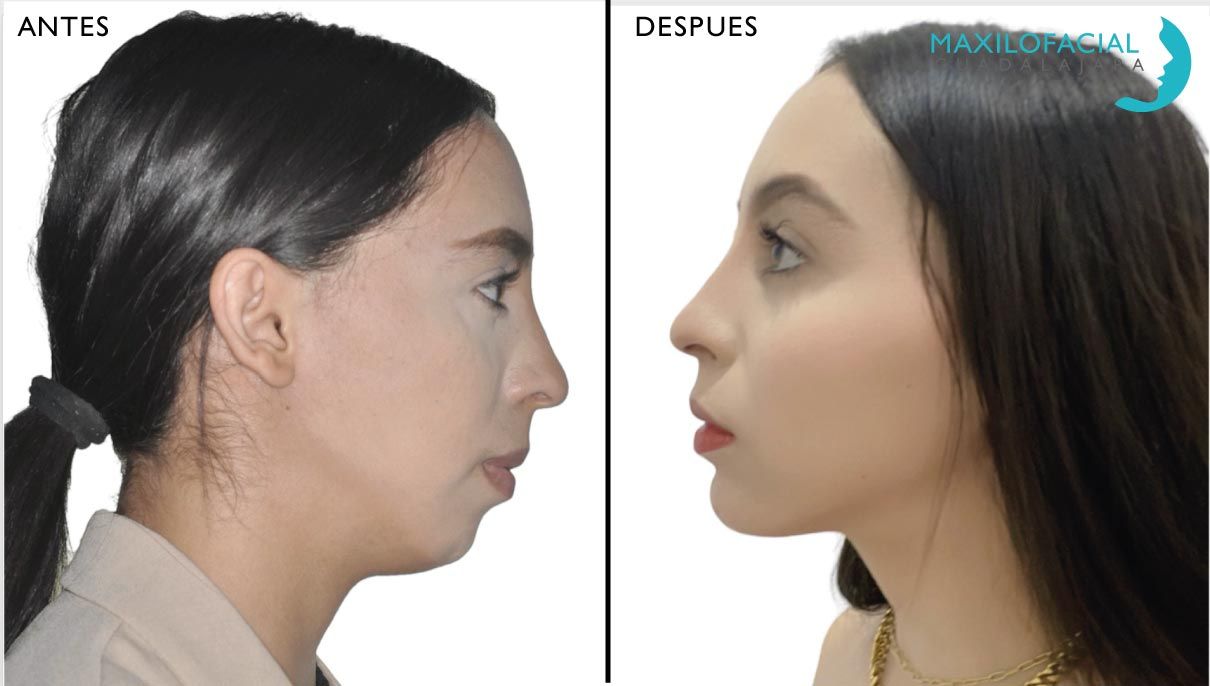

Cirugía de Mentón

La mentoplastia puede reducir o incrementar el tamaño de tu mentón, cambiar esto puede conseguir que un mentón poco definido aumente hasta conseguir dar más fuerza a tu personalidad. O bien que un mentón excesivamente prominente se reduzca suavizando tus facciones. Así mismo puede corregir asimetrías faciales mediante un procedimiento sencillo.

Se puede realizar bajo sedación o anestesia general, dependiendo del tipo del procedimiento. Generalmente la mentoplastia dura más o menos una hora, aunque los procedimientos complicados pueden durar más tiempo. El resultado final dependerá tu estructura facial, ya que este aspecto no es más que uno de los que conforman la apariencia de la cara.

Cirugía de Mentón

La mentoplastia puede reducir o incrementar el tamaño de tu mentón, cambiar esto puede conseguir que un mentón poco definido aumente hasta conseguir dar más fuerza a tu personalidad. O bien que un mentón excesivamente prominente se reduzca suavizando tus facciones. Así mismo puede corregir asimetrías faciales mediante un procedimiento sencillo.

Se puede realizar bajo sedación o anestesia general, dependiendo del tipo del procedimiento. Generalmente la mentoplastia dura más o menos una hora, aunque los procedimientos complicados pueden durar más tiempo. El resultado final dependerá tu estructura facial, ya que este aspecto no es más que uno de los que conforman la apariencia de la cara.